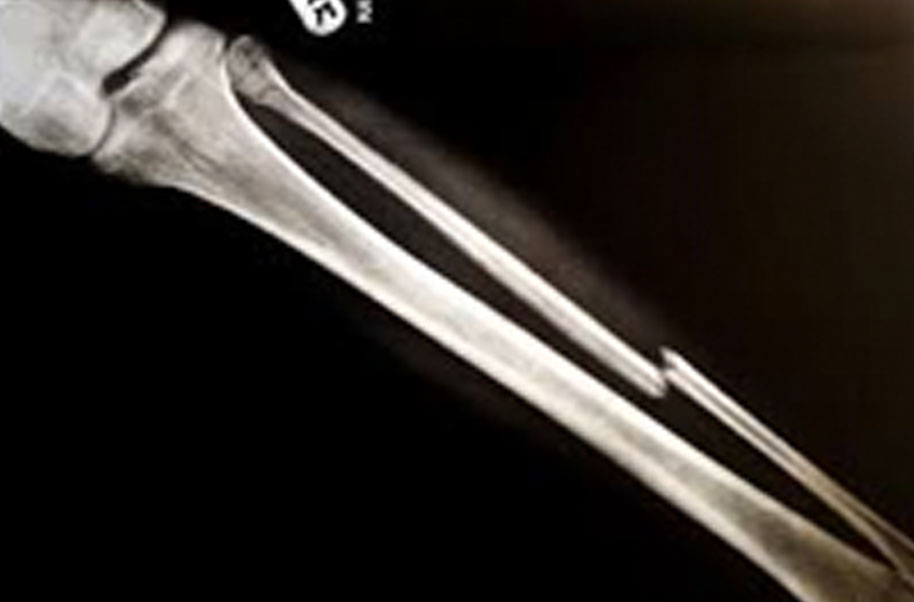

Manubrium (Broken Bone)

A complete or partial break in a bone.

- Treatment often involves resetting the bone in place and immobilising it in a cast or splint to give it time to heal. Sometimes, surgery with rods, plates and screws may be required.

Causes of bone fractures include trauma, overuse and diseases that weaken bones.